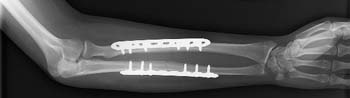

Open reduction and internal fixation with plates and screws. This is the most common type of surgical repair for forearm fractures. During this type of procedure, the bone fragments are first repositioned (reduced) into their normal alignment. They are held together with special screws and metal plates attached to the outer surface of the bone.

The broken bones of the forearm are held in position by plates and screws while they heal.